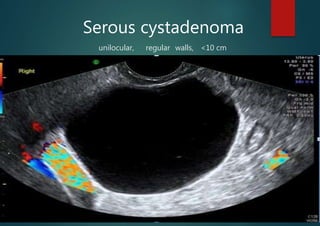

Serous cystadenoma

unilocular, regular walls, <10 cm